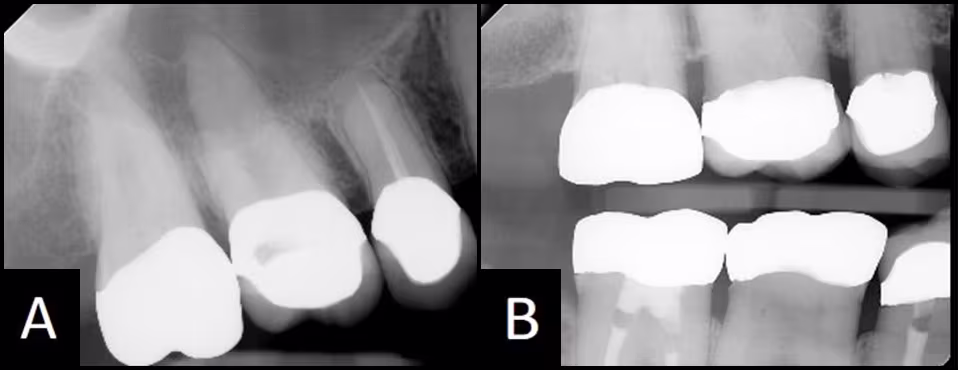

Problem #5: Comparison of periapical images versus bitewing images

Answer and Discussion: NO. The maxillary periapical image is created using +10 to +30 degrees of vertical angulation as compared to a bitewing that is usually created with +5 degrees. The greater vertical angulation changes the way the crown looks on the image. The buccal and lingual margins superimpose part of the root, making diagnosis of the margin impossible. Figure 28 compares a periapical and bitewing of the same crowns. Caries can only be diagnosed from this bitewing image, as the crown margins are covering the root immediately adjacent to the margin on the periapical image.

Figure 28 - Comparison of periapical and bitewing images of the same crowns in the same patient.

(A) The periapical image is not diagnostic for bone levels and crown margins. (B) The crown margins and bone are visible for examination on this ideal Bitewing image.